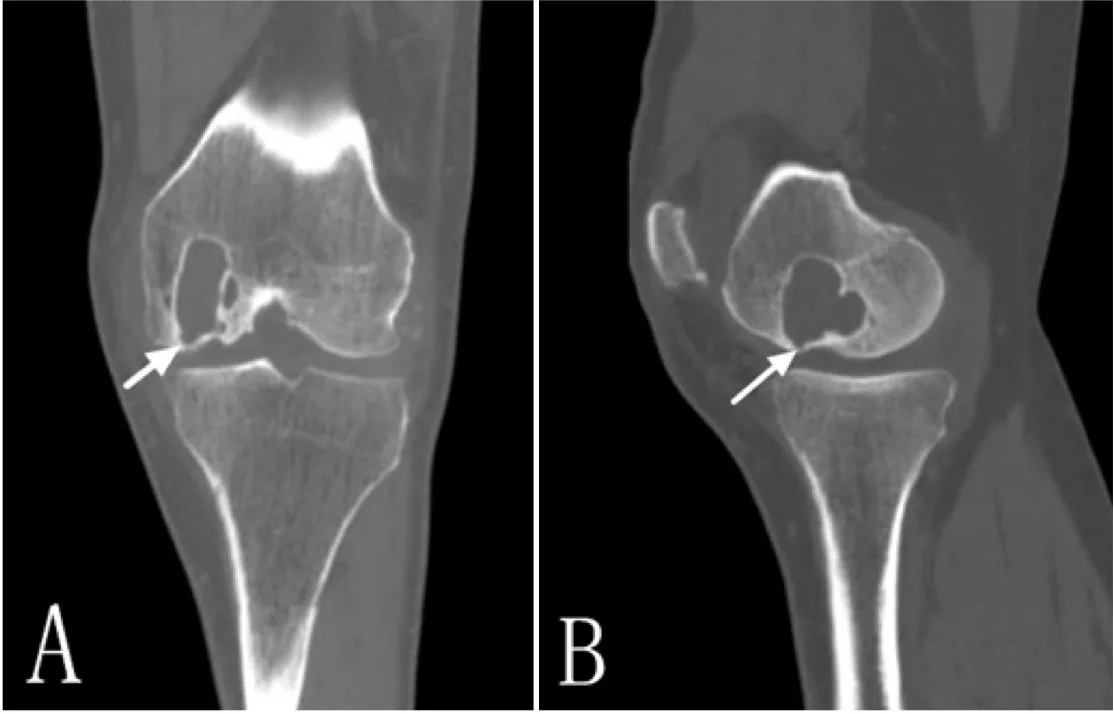

境界明瞭な空洞が骨内に形成されています.

その中の一人は, 脛骨の骨腫瘍を疑われて紹介された中高年の患者さんでした.

紹介元のMRIを確認すると, 変形性膝関節症に合併した骨内嚢腫(geode(ジオード):正式な日本語名はありません)が疑われました.

骨巨細胞腫や軟骨性腫瘍を否定するために, 造影MRIを追加撮影することにしました.

レントゲン写真やCTでは透けて見える円形または楕円形の『空洞』として観察されます.

17時前, 造影MRIを終えた膝の患者さんの画像を確認.

病変内部に造影効果が認められず, やはりgeodeと判断.